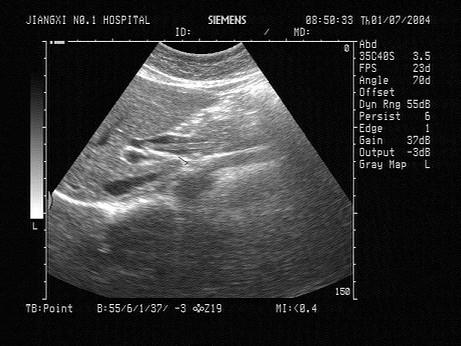

问题 女,25岁,上腹部剧烈疼痛数小时。皮肤巩膜无黄染,无发热,声像图如图所示,诊断为?(?)

选项 A.胆总管引流管回声 B.胆总管结石 C.胆总管蛔虫 D.胆总管胆汁淤积 E.胆总管癌

答案 C